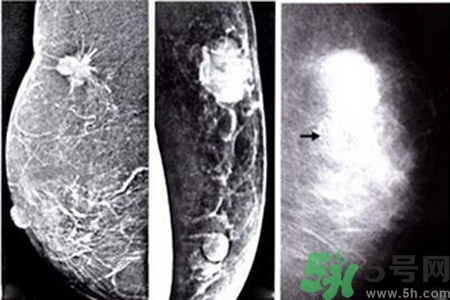

乳腺癌近幾年的發(fā)病率居高不下,女性朋友特別到了25歲之后,每年都要定期檢查乳房,已便及早發(fā)現(xiàn)疾病,盡快治療。醫(yī)院常用檢測乳腺癌的方法是采用乳腺鉬靶檢查,而診斷為乳腺鈣化的情況在這種檢查中顯示率也相當(dāng)?shù)母摺?/p>

乳腺鈣化是指可以在乳房造影看到鈣沉淀物,有多種因素可導(dǎo)致乳腺鈣化,如組織退變、壞死鈣鹽沉積,某些腫瘤分泌含鈣鹽的物質(zhì),使血管周圍組織鈣化。分析鈣化的形態(tài)、數(shù)目、部位以及與周圍結(jié)構(gòu)的關(guān)系,對辨別病變的性質(zhì)有較大的幫助。